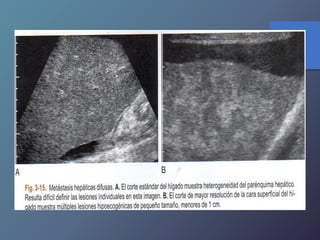

Metástasis

• Su incidencia depende del tipo de tumor.

• Localizaciones mas frecuentes del TU primario:

vesícula biliar, colon, estomago, páncreas, mama y

pulmón.

• Pueden presentar una sola lesión hepática, aunque

suelen tener múltiples masas focales.

Mt Hiperecoicas

• Ecográficamente se presentan las lesiones

de tamaño variable con presencia de un

halo hipoecoico.

• Diferenciar lesiones malignas de benignas

por presencia de halo hipoecoico.

• Se describen como lesiones ecógenas,

hipoecoicas, en diana, calcificadas,

quísticas y difusas.

Clasificación de las Metástasis